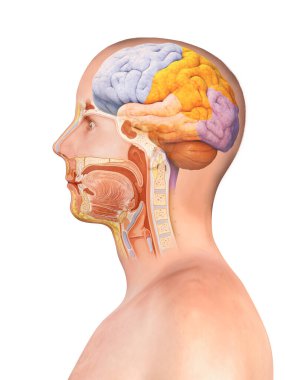

The arterial blood supply to the neck (carotids and vertebral arteries).

İnsanBaşıkanİlaçyüzboğazıBoyunresim çalışmasıprofilNormalbeyinarterkarotidKan damarıKan dolaşımıİnsan AnatomisiSerebral kan dolaşımıvaskülarizasyonsubclavian arteryortak Karotis arterbrachiocephalic Arteryel gövdeVertebral arterfacial arteryserebral artercervical arterytemporal arterydahili şah damarıharici şah damarıdeep cervical arteryBenzer İçerikler